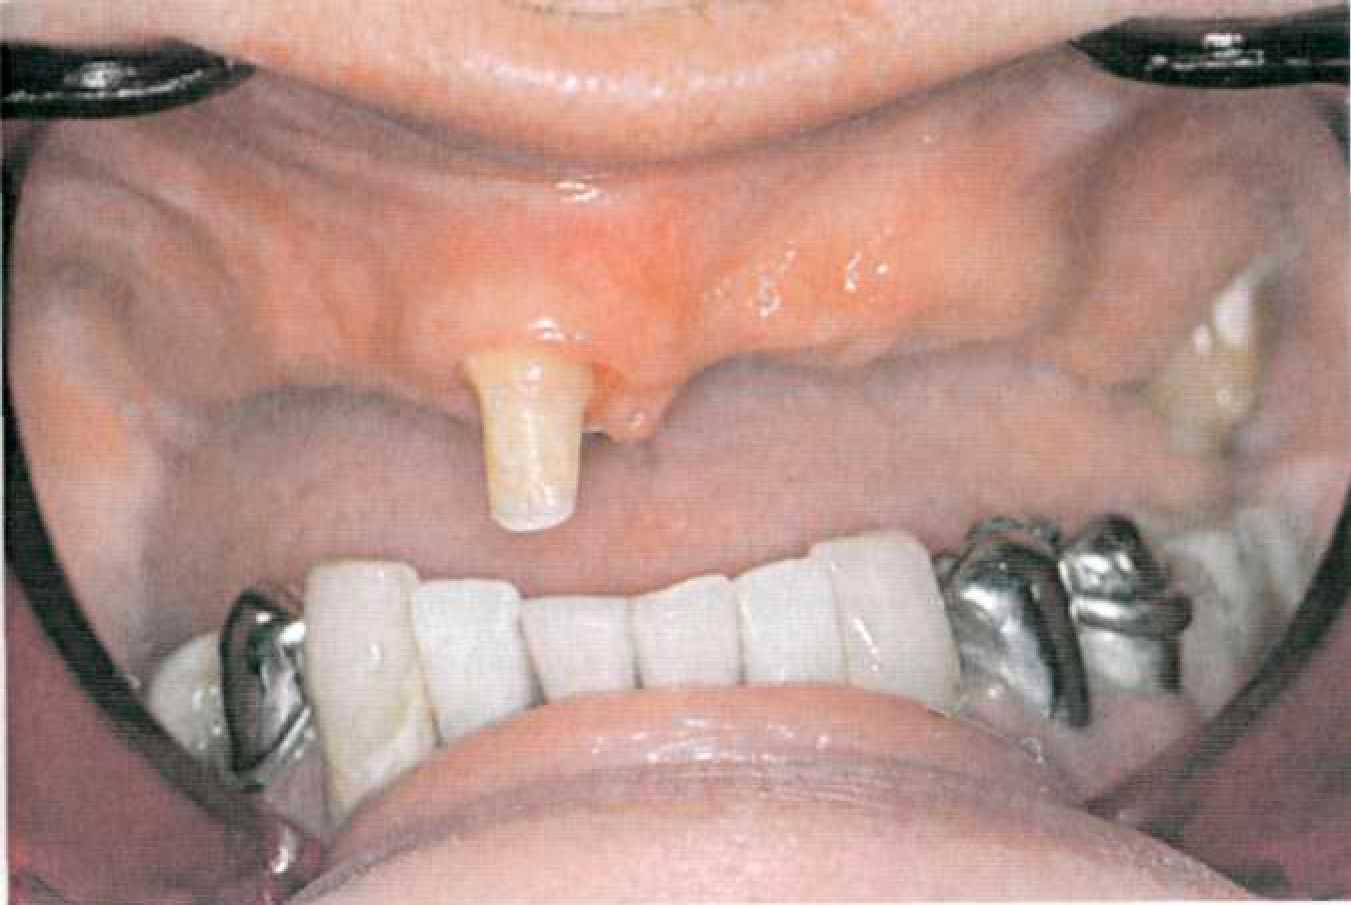

Покрывной протез с телескопическими фиксаторами с фрикционными штифтами Этап 1. После необходимого предварительного обследования, оценки ситуации в полости рта (рис. 127, 128) и санации снимают диагностические оттиски с верхней и нижней челюстей альгинатной массой стандартными ложками, подготавливают диагностические модели из прочного гипса.